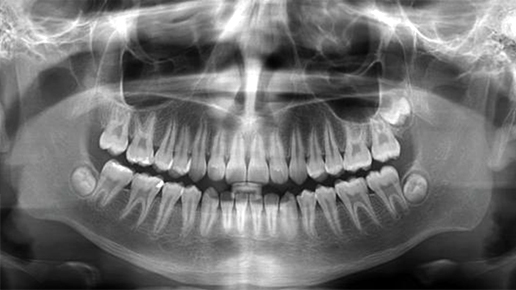

Radiologie numérique avec radiation minime:

Panoramique

La radiologie numérique permet un diagnostic très précis pour un traitement plus efficace!

Ce type de radiologie comporte plusieurs avantages :

Panoramique dentaire numérique